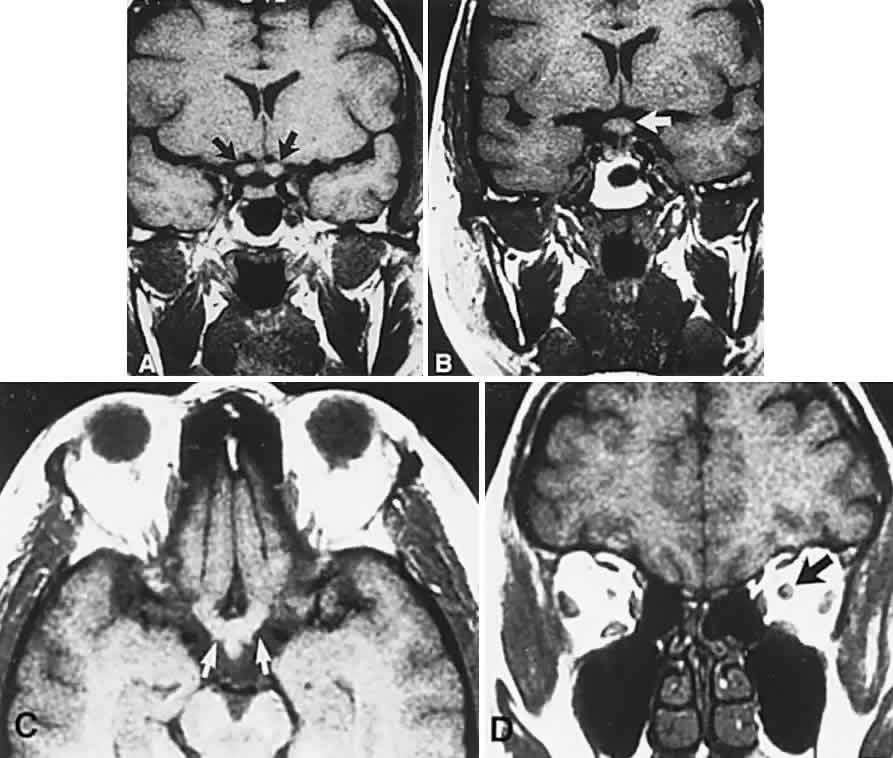

CT scanning retains special relevance to craniopharyngioma diagnosis, currently superior to MRI in detection of calcification and cyst formation (Fig. 7A to C); however, the extent of involvement of adjacent structures, that is, the optic chiasm, third ventricle, and intracavernous carotid artery, is more clearly delineated by MRI (Fig. 7D and E).93 Craniopharyngioma fluid collections are found to be uniformly bright on T2-weighted sequences, but on T1-weighted images, the signal intensity may range from hypointense to hyperintense, reflecting the heterogeneous contents of cysts. Because calcification and cyst formation are hallmarks of craniopharyngiomas, CT is more specific than MRI. At times, intrinsic infiltration of tumor may thicken the chiasm and contiguous optic nerve, a radiologic configuration that mimics glioma.94 Likewise, glioma may be simulated when the optic canal is invaded and enlarged, but accompanying bony erosion of the sella weighs heavily toward craniopharyngioma.

Fig. 7. Computed tomography scan of a large, multicystic craniopharyngioma. A. Axial section through the sella shows destruction of the bony skull base. Axial (B) and coronal (C) sections show cysts (white arrows) and calcification (arrowheads). Contrast-enhanced magnetic resonance imaging of the craniopharyngioma. Sagittal (D) and coronal (E) sections with gadolinium show solid and cystic (arrows) portions.